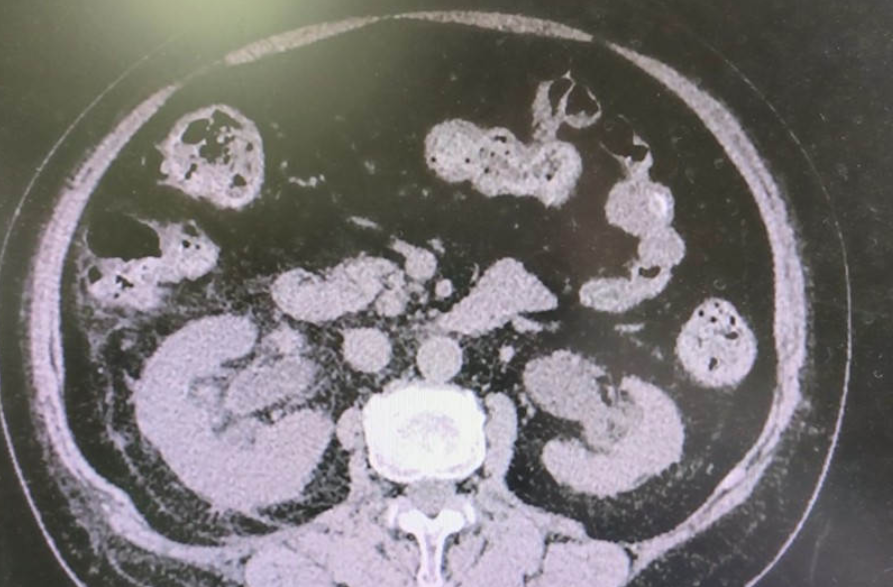

【检查】:泌尿系CT平扫:1.膀胱内见范围约5×4cm新生物,侵犯双侧输尿管开口;2.双侧上尿路积水扩张。肌酐:713mmol/L。

【临床诊断】:1、膀胱新生物:膀胱癌?;2、肾功能衰竭;3、双肾积水

【治疗经过及结果】:行膀胱镜检查发现新生物完全遮挡双侧输尿管开口,无法置入输尿管支架管。故行双侧经皮肾穿刺造瘘术以解除梗阻。

患者右肾积水少,术中采用B超定位(如下图),反复调整进针角度终获成功。拟待肾功能恢复后再行腹腔镜膀胱癌根治术。